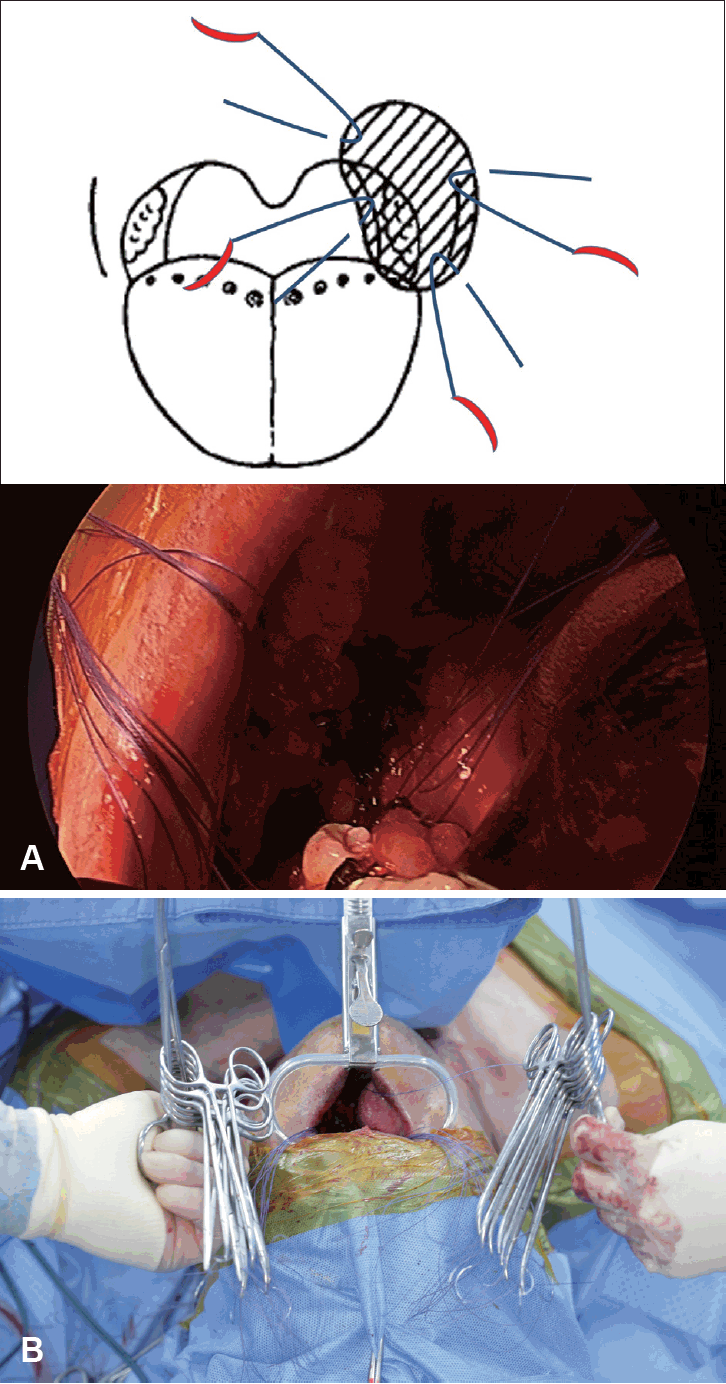

경부림프절 절제술(neck dissection) 및 두경부암 원발부위 절제술을 마치고 나면 유리피판을 거상하기 전 결손부위 봉합을 시작하게 된다. 허혈시간(ischemic time)을 줄이기 위해 피판거상 전 절제연의 봉합을 먼저 시행한다. 절제연의 점막(mucosal edge of surgical defect)을 바늘을 분리할 수 있는 3-0 흡수성 봉합사(vicrylⓇ 3-0 pop-off suture)를 이용하여 바이트(bite)를 시행한 후 모스키토 클램프(mosquito surgical clamp) 등을 이용하여 고정해둔다(Fig. 1A and Supplementary Video 1). 이때 실(string)의 순서가 바뀌지 않도록 주의해야 한다. 보통 좌우를 나누어 봉합사들을 두 개 혹은 세 개의 그룹으로 나누어 고정해두는 것이 나중에 피판을 삽입할 때 구분이 용이하며 봉합사의 바늘이 떨어지지 않도록 주의한다(Fig. 1B). 이후 계획된 유리 피판의 거상을 시작한다.

피판 삽입 및 봉합(Flap inset and suture through the flap)

피판을 거상한 이후, 피판을 두경부 결손부위에 위치시킨다. 혈관경(pedicle)을 문합할 혈관부위, 상갑상동맥(superior thyroidal artery)이나 안면동맥(facial artery) 등 주변에 위치시킨 후 피판과 결손부위의 봉합을 시작한다. 이미 결손부위에 위치한 봉합사를 순서에 맞추어 피판에 바이트를 한 이후 봉합사의 바늘을 당겨서 제거하고, 다시 한 번 순서에 맞추어 모스키토 클램프를 이용해 고정한다(Fig. 2 and Supplementary Video 1). 이때 봉합은 구강 바깥의 넓은 공간에서 피판의 적절한 위치를 안전하게 확인한 후 시행할 수 있다. 모든 봉합사의 바이트를 시행한 이후에 봉합사의 결찰 단계로 진행한다. 이때 역시 실의 순서 및 좌우가 혼동되지 않도록 잘 구분해 두는 것이 매우 중요하다.

봉합사 결찰(Tie the knot of unlocked strings)

구강 바깥쪽 넓은 공간에서 봉합을 시행한 피판을 결손부위로 적절하게 밀어 넣은 이후 순서대로 결찰하지 않은 봉합사의 결찰을 순차적으로 시행한다. 이미 절제연과 피판의 바이트는 적절한 위치에 위치시켰으므로 결찰은 시야에서 정확하게 확인하지 않고 진행해도 무방하다. 보통 가장 안쪽, 아래쪽 봉합사부터 결찰을 시행하며, 수술기계를 이용한 결찰보다는 양손을 이용한 결찰(tie the knot)이 빠르고 정확하게 진행할 수 있다(Fig. 3 and Supplementary Video 1). 이때도 봉합사의 순서가 바뀌지 않도록 주의해야 하며, 실이 엉키는 것도 주의해야 한다. 이후 봉합이 부족한 부분의 봉합을 추가로 시행하면 피판 삽입을 끝내고 미세혈관 유합술(microvascular anastomosis)로 진행할 수 있다.